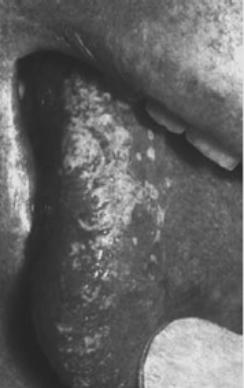

1.1.2 Candidosi

linguale

1.1 Candidosi

Infezione

da fungo „tipo lievito¾ (candida albicans) del cavo orale, lingua, vulva,

vagina e glande specialmente in uno stato debole del sistema immunitario.

Sintomi:

strato biancastro, perdite biancastre femminili (leucorrea), prurito, caduta

epidermide/mucosa, emorragie.